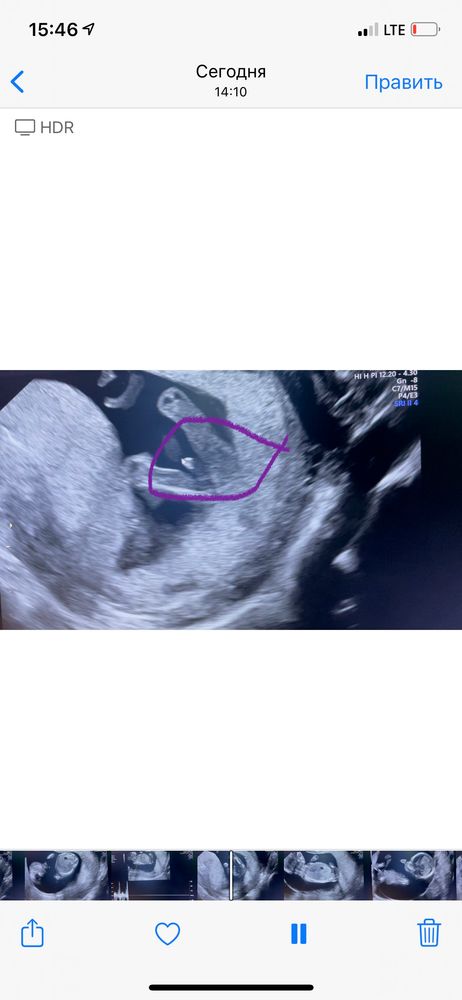

1 скрининг, у нас будет сынок❤️

Поздравляю вас😄😎а скажите это уже так хорошо видно,какой срок?13 неделя?

СоФоЧкА , спасибо большое ❤️ сегодня 12+5, я сама удивилась, что так рано ☺️